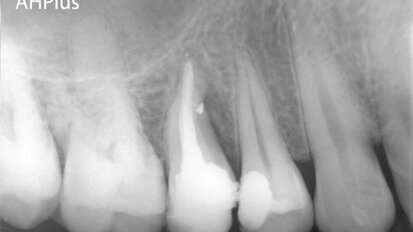

MounceFiles:A safe, economical and efficient option for canal preparation

Opinions vary as to the best means to achieve three dimensional, cleansing, shaping and obturation of the root canal system. Emerging technology, literature...